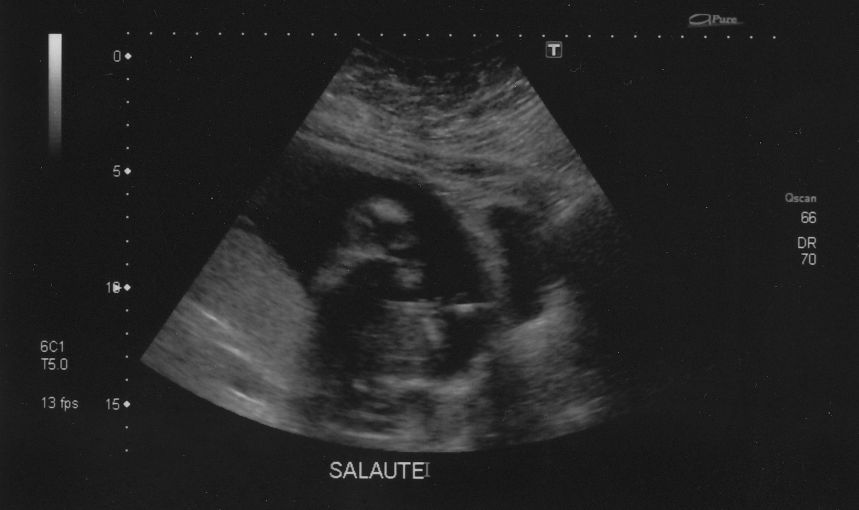

Danyoo wrote:The technician was having a hard time getting measurements because Cody was so active. "If I could just get baby to stop moving for a tenth of a second...I could measure his femur!"